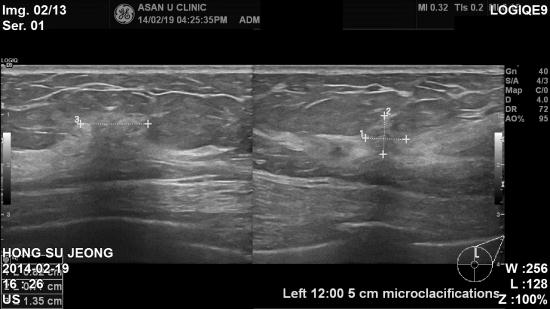

아산유외과 개원 후 67번째 유방암진단.

건강검진에서 실시한 유방암검진상 이상소견으로 내원하신 54세 여자분이십니다.

유방촬영상 좌측유방에 미세석회화 소견이있었고

유방초음파검사상에도 좌측유방 12시방향에 석회화를 포함하고 있는 결절이있어

조직검사결과 유관상피내암으로 진단되었습니다.

건강검진에서 치밀유방, 또는 석회화 소견이있을경우에는 전문의와 상담하시고

정밀한 초음파 검사가 필요합니다.